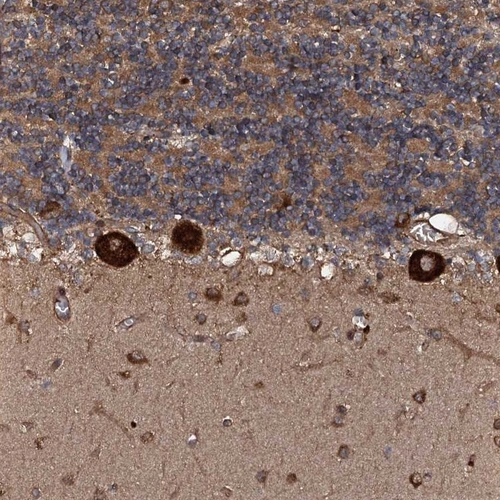

Immunohistochemical staining of human cerebellum shows strong cytoplasmic positivity in purkinje cells.